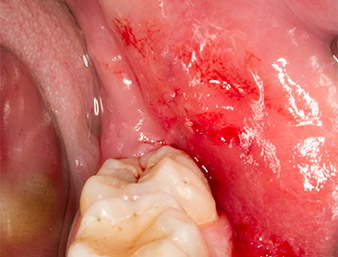

Ein 26-jähriger Patient hatte sechs Monate nach Osteotomie des Zahnes 38 wiederkehrende Schmerzen im Operationsbereich und klagte über Hyposensibilität im Ausbreitungsgebiet des Nervus alveolaris inferior. Er wurde vom überweisenden Zahnarzt, der die ursprüngliche Zahnentfernung nicht selbst durchgeführt hatte, an die Abteilung für Orale Chirurgie der Universitätszahnklinik Wien überwiesen.

Der Wurzelrest regio 38 zeigte bereits in der Panoramaschichtaufnahme eine enge Lagebeziehung zum Nervus alveolaris inferior. (Abb. 1)

Abb. 1: Panoramaschicht-Aufnahme 6 Monate nach Osteotomie Zahn 38: Radix relicta liegt nahe dem Nervus alveolaris inferior.

Nach Leitungs- und Lokalanästhesie wurde das Operationsfeld für einen bukkal-retromolaren Zugang weichgewebig eröffnet und dargestellt (Abb. 3).

sulkuläre Schnitt

Abb. 3: Der sulkuläre Schnitt beginnt Mitte des Zahnes 36, mit distaler Verlängerung am aufsteigenden Ast.

Das Gewebe über dem Wurzelrest war nicht vollständig verknöchert und bestand zu einem großen Teil aus entzündlich verändertem Granulationsgewebe (Abb. 4).

Granulationsgewebe

Abb. 4: Zwei Langenbeck-Haken und ein Raspatorium nach Prichard stellen das OP-Feld dar. Granulationsgewebe der unvollständig abgeheilten ersten Osteotomie ist zu erkennen.